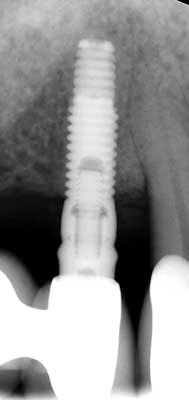

2-year postop radiograph with PD 3-4 mm around No. 5 implant and No. 6 natural tooth

- Patient presented back to our office with 3-4 mm probing depth and now has a stable result for not only the tooth but also the implant